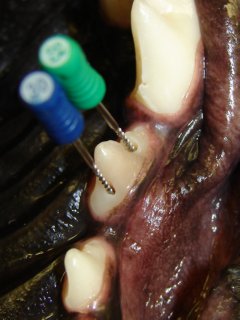

Upper third premolar tooth’s inside is being cleaned with endodontic files.

Third premolar tooth is filled with an inert material.